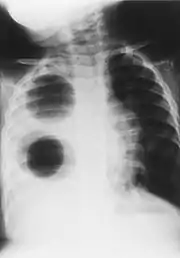

Chest radiograph of a woman with unilateral pulmonary agenesis | |

- Chest X-ray is effective in detecting the traits of lung herniation.[1] The unaffected side of lung tends to undergo hypertrophy, and move towards the empty space in the chest wall on the opposite side.[1] This herniation could be indicated by fluoroscopy.[1] With age increasing, the herniation progresses and ease its detection.[1]

- Electrocardiogram is useful in detecting dextrocardia, a possible outcome when agenesis is present on the right lung.[1] With empty space in the chest wall, the heart rotates in clockwise direction, shifting the location for apex beat occurrence.[1] Hence cardiac physical examination also helps as heart sounds is heard best at right chest with dextrocardia.[1][4] In the condition of left side agenesis, heart sounds will appear to be louder than normal.[1][4]

- Chest asymmetry, as a possible trait for pulmonary agenesis, is found to be more obvious in adult patients, especially in males.[4] Breast development in females tends to make it less obvious for the observance of asymmetry, though it could still be indicated by a more conical shape and slightly higher location of the breast on the affected side.[4]